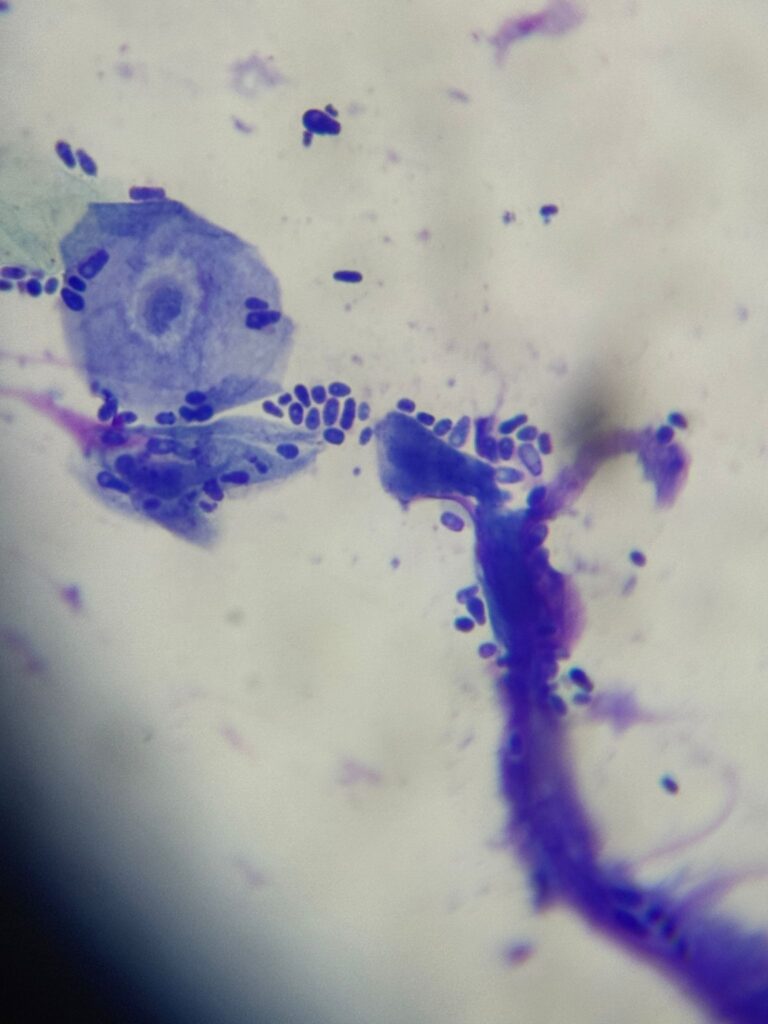

badania cytologiczne skóry i przewodu słuchowego,

testy diagnostyczne w kierunku infekcji bakteryjnych i grzybiczych,